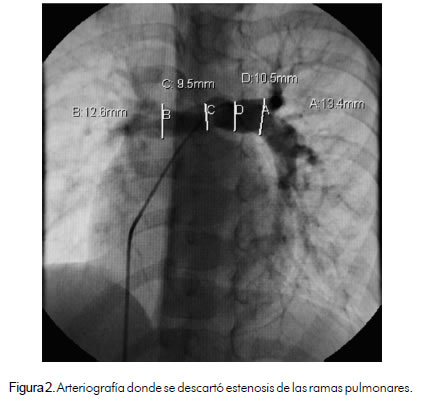

Paciente de 6 años de edad, de género masculino, previamente asintomático, practicante de patinaje, quien tenía controles por cardiopatía congénita en otra institución y fue remitido a la nuestra para valoración especializada y estudios complementarios. El ecocardiograma reportó drenaje venoso anómalo parcial de una vena pulmonar a la vena innominada y estenosis leve de las ramas pulmonares. La radiografía de tórax mostró cardiomegalia a expensas del ventrículo derecho. Se realizó angiografía que reportó conexión venosa anómala pulmonar parcial de dos venas pulmonares a una vena vertical con drenaje de ésta a la vena innominada, sin obstrucciones, Qp/Qs de 2.3:1 y presiones pulmonares normales; se descartó estenosis de las arterias pulmonares (figuras 1 y 2). Fue enviado a cirugía para realizarle toracotomía lateral izquierda (figura 3); se identificaron y disecaron venas pulmonares izquierdas, vena vertical y vena innominada, y se hizo anastomosis termino-terminal del extremo distal de la vena vertical con la orejuela izquierda (figura 4). Ingresó a la unidad de cuidado intensivo donde se vigiló por dos días y posteriormente fue trasladado a piso; luego se le dio de alta en buenas condiciones.